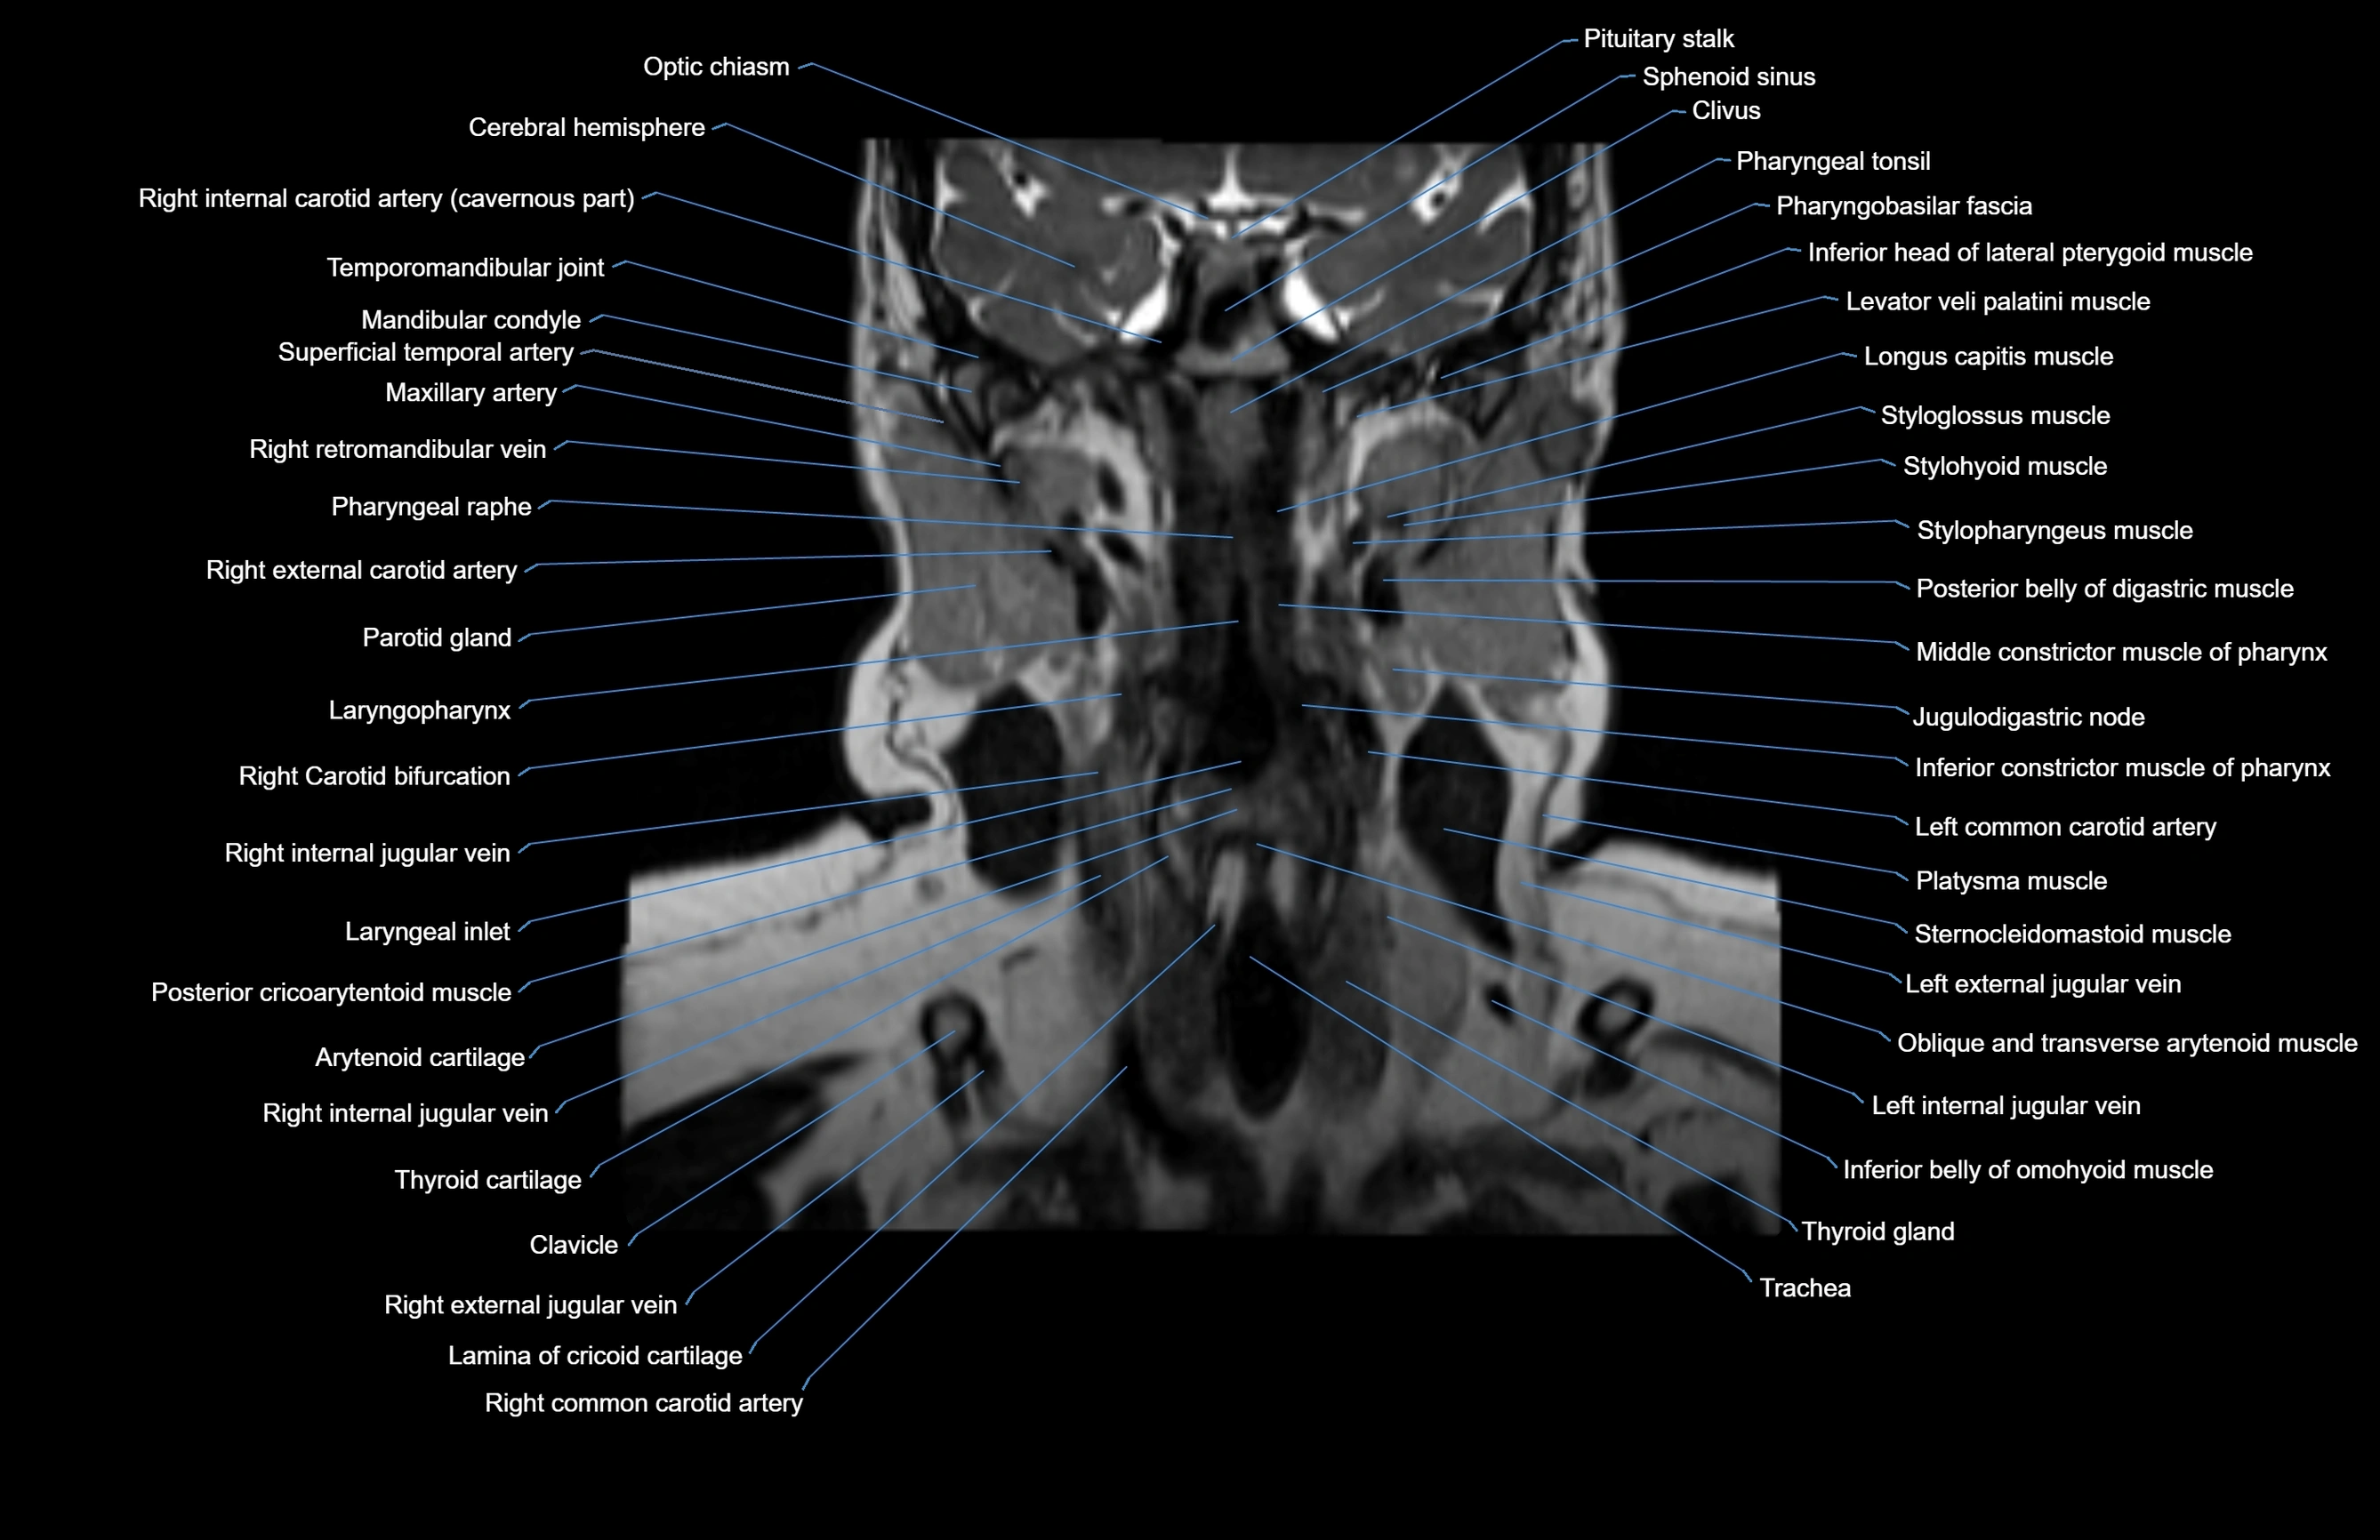

- Arytenoid cartilage

- Carotid bifurcation

- Clivus

- Common carotid artery

- External jugular vein

- Inferior belly of omohyoid muscle

- Inferior constrictor muscle of pharynx

- Jugulodigastric lymph nodes

- Lamina of cricoid cartilage

- Laryngeal inlet

- Laryngopharynx

- Left common carotid artery

- Mandibular condyle

- Middle constrictor muscle of pharynx

- Optic chiasm

- Palatine tonsil

- Parotid duct

- Parotid gland

- Pharyngeal raphe

- Pharyngeal recess

- Pharyngeal tonsil

- Platysma muscle

- Posterior belly of digastric muscle

- Sternocleidomastoid muscle

- Sternohyoid muscle

- Sternothyroid muscle

- Thyroid cartilage

- Thyroid gland

- Trachea